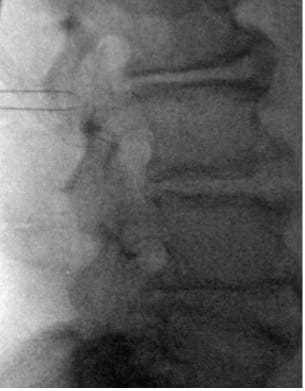

| True Lateral View |

|

- Place marker 22G or 25G spinal needles bilaterally at L3 TP–SAP junction; confirm tip at superior TP border on the lateral view.

- In PA view, introduce guide needle just off midline from the superior L4 SP border towards the ipsilateral L3 TP–SAP junction marker; in lateral view, advance anteriorly to TP to traverse L2–L3 intertransversarii (~45°).

- In the lateral view, advance the guidewire towards the inferior dorsal L2 body; adjust depth if resistance is encountered. Prior to removing the guide needle and exchanging for the introducer sheath/dilator, use a #11 scalpel to make a stab incision along the guide needle trajectory adjacent to the L4 SP to create room for the introducer sheath/dilator.